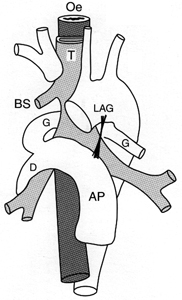

L’atteinte cardiaque peut se faire par propagation de voisinage en cas de tumeurs bronchiques ou médiastinales (A), par voie hématogène en cas de métastases à distance (cf: métastase intra-myocardique d’un cancer ORL illustrée en B), par voie lymphatique ou veineuse prenant les cavités cardiaques droites comme dans les exemples ci-dessous d’extension d’un EOA utérin enclavée dans l’infundibulum (C) ou de tumeur de Grawitz envahissant l’oreillette droite (D).